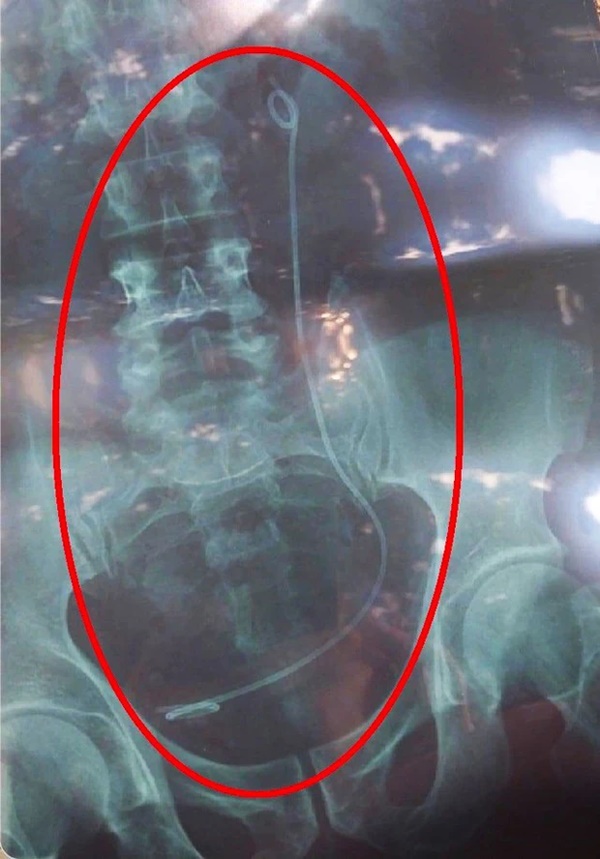

Tuy nhiên, sau khi tiến hành nội soi, ê-kíp thực hiện không tìm thấy đoạn ống nhựa như phim X-quang thể hiện. Lúc này, bộ phận chức năng tiến hành rà soát phát hiện người của bệnh viện đã đưa nhầm kết quả chụp X-quang của một bệnh nhân khác cho ông H..

Phim chụp X-quang có sợi dây trong ổ bụng là của bệnh nhân khác nhưng trao nhầm cho ông H.